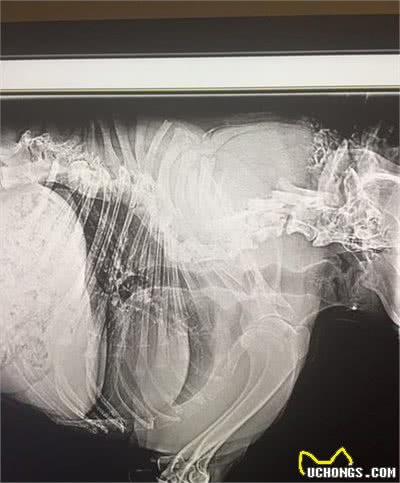

头和四肢都是正常尺寸,就是脊椎比一般的狗狗要短得多,背部不是平直的,而是倾斜的,几乎没有脖子,也就是说头下面直接就是身体,脖子部分似乎被移除了,尾巴也是畸形的,呈螺旋状。

恰好是因为它的外观设计,让它变成了一只流浪犬。当援救机构发觉后,对它完成了救护,查验后发觉,它缺失了几片脊椎,没法根据整形手术开展修补,只有实现简洁的小尾巴修补和创伤医治。

幸运的是,卡西莫多狗并没有因为脊椎的缺少,而失去日常的活动能力,没有脖子,它就没有办法转头,只能整个身体转过来,也不能正常低头去闻嗅物体。